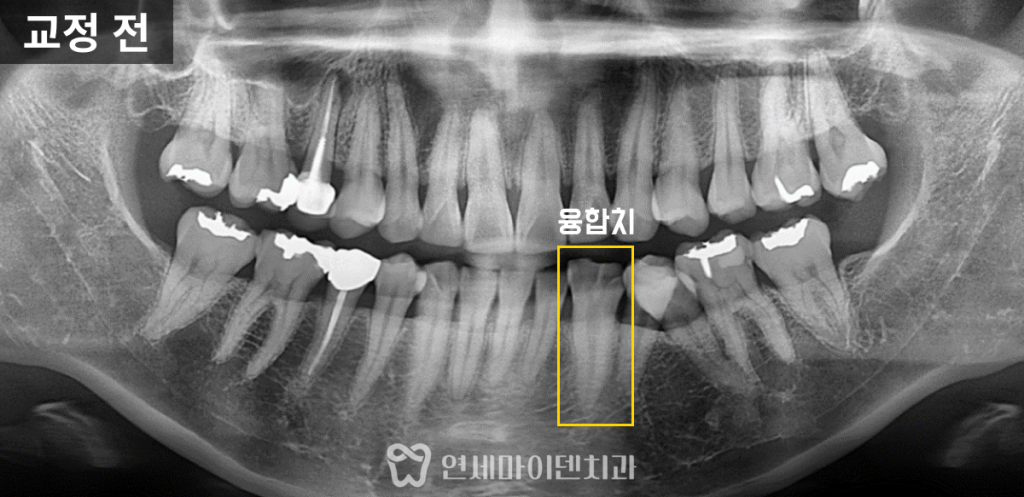

융합치로 인한 비대칭과 부정교합

이 환자분은 30대 여성분으로

고르지 못한 치열과 비대칭 때문에 저희 병원에 오셨습니다.

정밀 검사 결과, 왼쪽 아래 두번째 작은 어금니와 송곳니가

하나로 붙어있는 융합치였습니다.

또, 치축이 왼쪽으로 기울어져 있었고,

왼쪽 앞니의 위치도 약간 틀어져 있는 상태였습니다.

이 환자분은 왼쪽 치아의 길이가 상대적으로 짧고

그로 인해 중심선이 왼쪽으로 치우친 모습이었습니다.